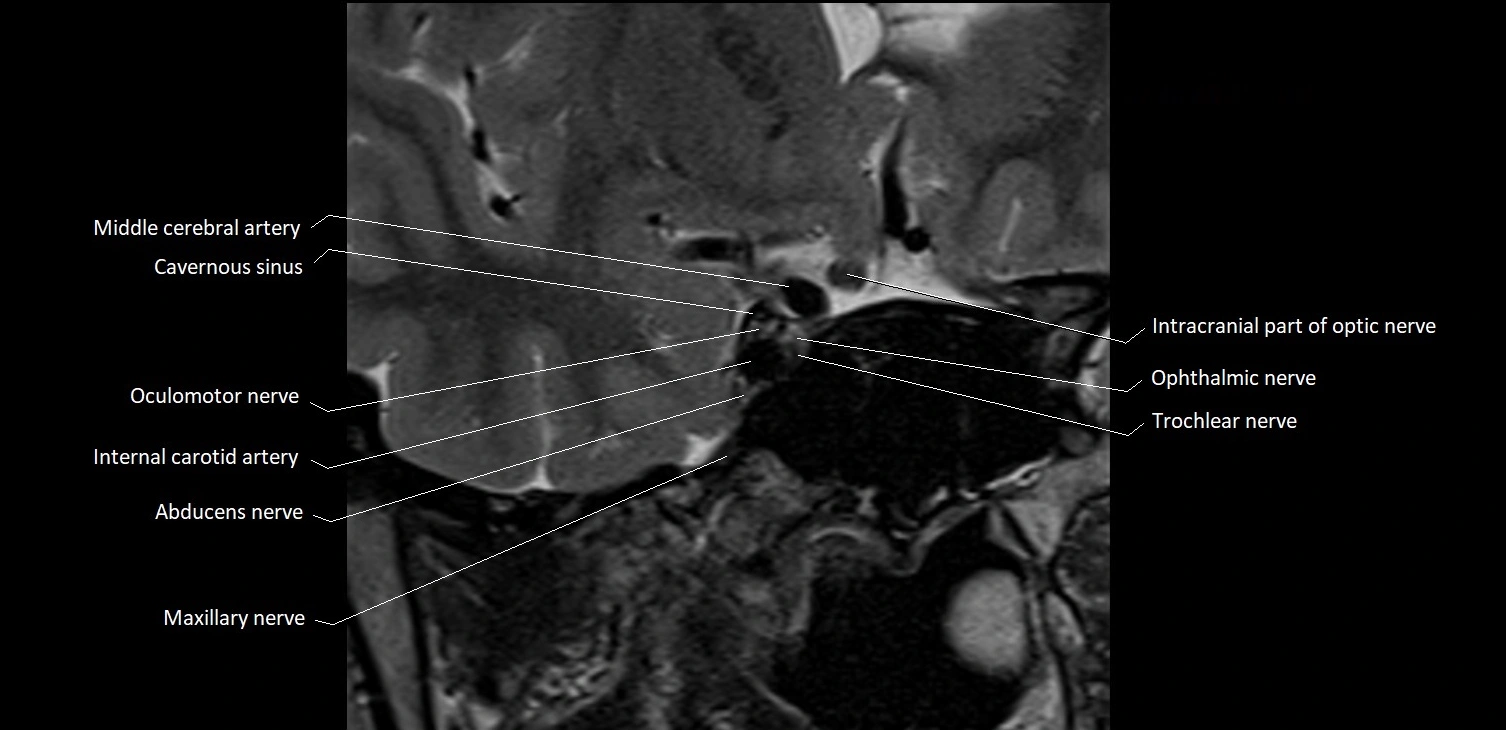

MRI images